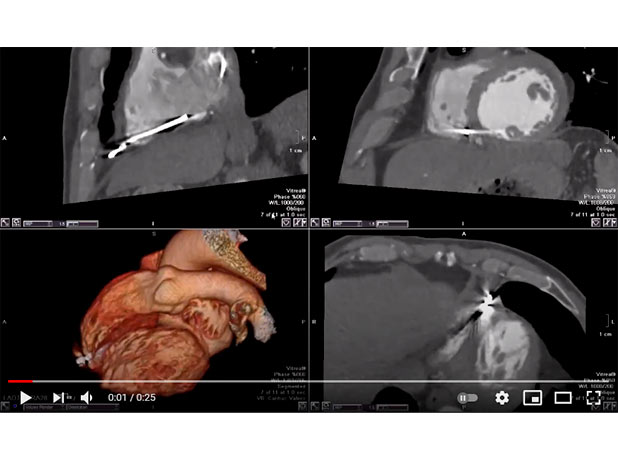

VVI PACEMAKER WIRE PERFORATION

Mohamed Gibreel , FEBR (Fellowship of Egyptian Board of Radiology ) Cardiac imaging consultant at Aswan heart center -Magdi Yacoub Foundation , Egypt